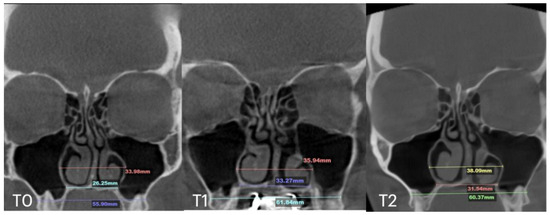

2.7. Case D: Midfacial Asymmetry Correction with Guided Expansion

| Case D | 26.25 | 33.27 | 31.54 | 55.9 | 61.84 | 60.37 | 33.98 | 35.94 | 38.09 | 29.77 | 29.24 | 29.02 | 6.2 |